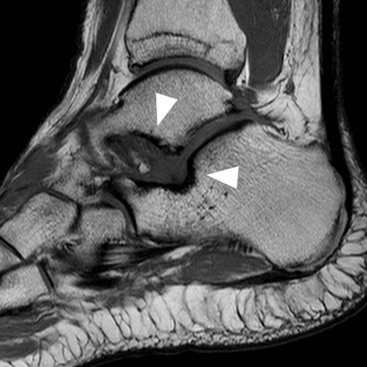

Impingement may occur in various locations around the ankle, the commonest types being anterolateral (see above), anterior and posterior. Anterior impingement occurs between bony spurs on the dorsal talar neck and anterior tibial plafond, a condition associated with kicking activities like soccer. These spurs can be readily identified on lateral radiographs. MRI may additionally reveal synovitis and lateral ankle ligament damage.41 Posterior impingement is most frequently associated with a large os trigonum or Stieda process of the talus (Fig. 46-59). These give rise to chronic compression of soft tissues against the posterior tibia in activities that involve repetitive forced plantar flexion as in ballet dancing.42